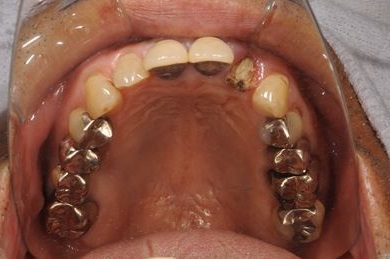

| 性別/年齢 | 男性 / 61歳 | ||||||||||||||||||||||||||||||||

| 主訴 | 奥歯のインプラント治療を希望。 | ||||||||||||||||||||||||||||||||

| 治療方針 | インプラント治療にて、機能的・審美的回復を行う。 | ||||||||||||||||||||||||||||||||

| 治療内容 | インプラント4本、メタルボンドセラミッククラウン4本 | ||||||||||||||||||||||||||||||||

| 総治療費 | 1,508,220円 | ||||||||||||||||||||||||||||||||

| 治療期間 | 7ヶ月 |